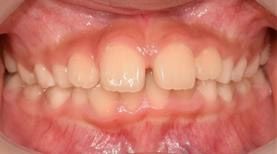

보통 아이들은 6~7세가 되면 유치가 빠지고 영구치 맹출이 시작되는데, 이때 앞니가 가지런하지 못하거나 치아 사이가 벌어지는 일이 많이 발생해 치아교정 상담을 고민하는 부모가 많다.

관악서울대치과병원 이미영 교수(치과교정과 전문의)는 이 시기가 ‘미운 오리 새끼 단계’라고 불리는 시기로, 앞니 사이가 약간 벌어져 있거나 치아 배열이 고르지 않은 정도는 모두 정상으로 간주한다고 설명했다.